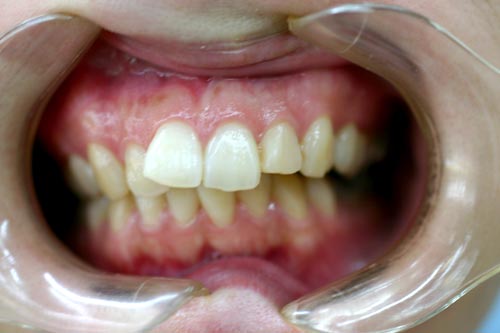

上顎の中央の歯一本が前にとびだしている治療例

After

上顎の中央の歯一本が前にとびだしている症例です。これだけ前に出ていると、歯を抜いて並べていくか、何本かの歯を削らないときれいに並べられません。

このケースは、上の顎に矯正用のミニスクリュー{矯正用ミニインプラント}を入れて、歯を抜かず、削りもしないで、しかも上顎だけの矯正で治した症例です。

矯正用インプラントを使うことによって歯並び全体を後方に動かすことができるようになったため、このような治療ができるようになりました。

年齢 20代

治療期間 8ヶ月

治療費用 800,000円

治療のリスク 特になし